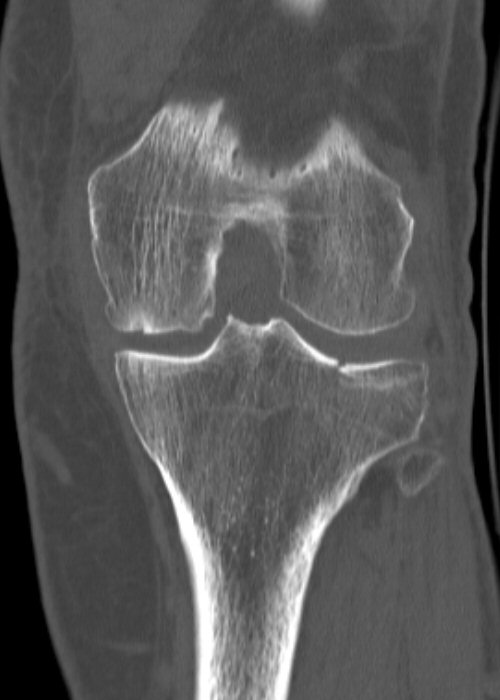

Till vänster exempel på odislocerad fraktur i laterala tibiakondylen, behandlad icke-kirurgiskt. Högra bilden efter 2 år, börjat utveckla artros.